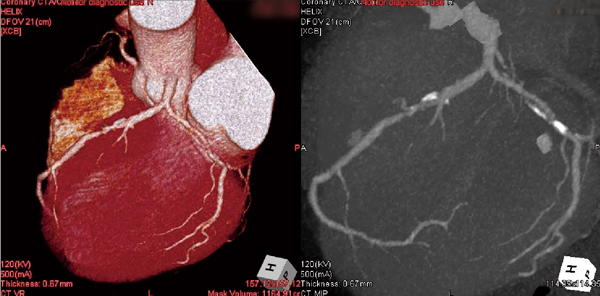

中外医学社 | 書籍詳細。臨床心臓CT学-基礎と実践マネージメント | 小山 靖史, 鈴木 諭。アプリケーション(心臓領域) | REVORAS。【N☆】令和6年(新米)コシヒカリ1等米10キロ。CT検査 | 戸畑共立病院。オプション検査 | 人間ドック健診センター | 大田区蒲田 牧田。。桜橋渡辺未来医療病院 MDCT検査予約。医学出版_循環器ナーシング16年6月号。CT検査 | 戸畑共立病院。心臓特化型画像診断センター「心臓画像クリニック(CVIC)飯田橋。朝倉書店『内科学』(第12版)デジタル付録。メジカルビュー社|診療放射線技師|心臓CT活用マニュアル。心臓Ⅰ:Step and shoot technique 岩城 卓(横浜栄共済病院。「臨床心臓CT学 基礎と実践マネージメント」小山 靖史定価: 22000円 (20000円+税)ぼぼ未使用でパラパラと見ただけで、状態はよいと思われます。書き込みも見返しましたがありませんでした(万が一あったら申し訳ございません)。表面に多少のスレやキズはあります。また天面に名前の印鑑がありマジックで消しています。あくまで写真のものをお渡しということでよろしくお願い致します。ご質問や価格交渉ありましたらメッセージくださいm(._.)m循環器内科、内科、カテ、カテーテル、CAG、PCI、FFRインターベンション、読影、放射線冠動脈、動脈硬化冠動脈疾患、虚血性心疾患、狭心症、心筋梗塞高血圧、糖尿病、脂質異常症、肥満